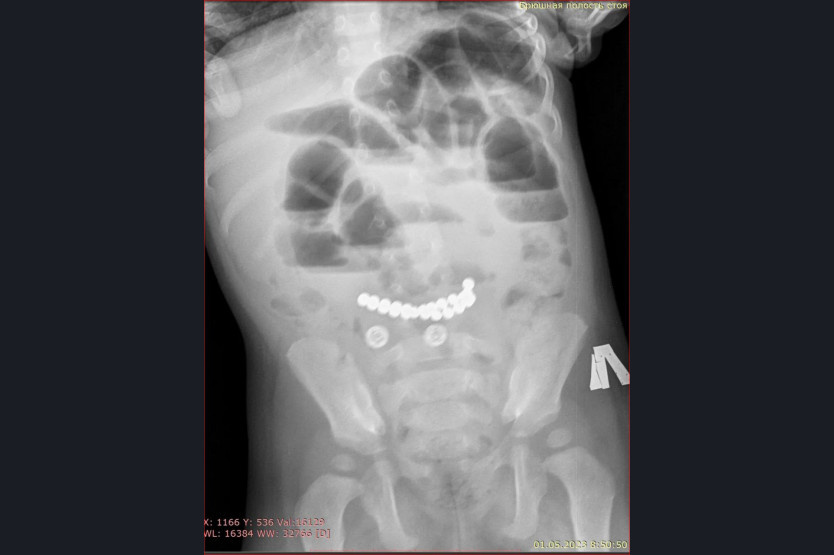

«Особую тревогу вызывают случаи, связанные с магнитами. Недавно в наше приемное отделение поступил ребенок с жалобами на многократную рвоту и сильные боли в животе. Обследование выявило множественные рентгенконтрастные предметы в кишечнике и явные признаки кишечной непроходимости. В ходе экстренной операции было удалено 25 магнитов», – рассказала главный врач ДГКБ № 1 Евгения Аверкина.

Магниты могут притягиваться друг к другу через стенки кишечника, это приводит к кишечной непроходимости, некрозу, перфорации кишечника и формированию свищей. К сожалению, длительное нахождение 25 магнитов в желудочно-кишечном тракте у этого пациента привело к серьезным осложнениям. Но сейчас жизни ребенка ничего не угрожает, операция прошла успешно. К сожалению, ежегодно пациентами хирургического отделения Детской городской клинической больницы № 1 становятся несколько детей, из желудочно-кишечного тракта которых врачи извлекают инородные тела.